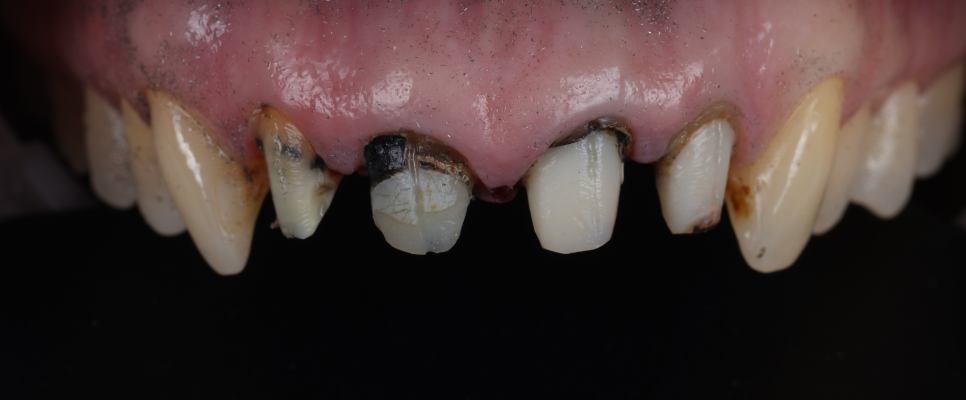

앞니 크라운 검은 선 때문에 오시면 많은 분들이 이렇게 말씀하세요.

'그럼 이번에 새로 만들면 되겠네요?'

그런데 진료를 해보면 겉에 씌워놓은 보철 자체는 멀쩡한데 앞서 말씀드린 대로 치아 내부 색이 문제인 경우도 있는데요.

이럴 때 크라운만 새로 만들면 겉은 새것인데 안쪽 치아 색은 그대로라 결과가 기대만큼 자연스럽지 않을 수 있고 시간이 지나 또 똑같은 문제가 발생할 수 있어요.

치아 내부 변색이 원인이라면

실활치 미백을 해야 합니다.

실활치 미백은 치아 안쪽에 미백제를 넣어서 치아 색을 안에서부터 밝게 만드는 과정이에요.

신경치료 후 어두워진 색상이나 신경이 죽은 경우 등 내부 변색이 원인일 때는 실활치 미백을 진행한 뒤 치아 색이 충분히 밝아지면 그다음 단계에서 새로운 크라운을 제작하고 있어요.